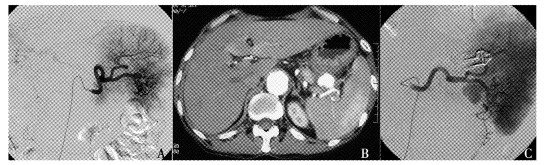

结果  6例假性动脉瘤中3例位于脾动脉, 另3例分别位于胃十二指肠动脉、胃网膜右动脉和胰十二指肠下动脉。增强CT发现4例, 全部通过数字减影血管造影(digital subtraction angiography, DSA)明确诊断并采取经导管动脉栓塞治疗, 技术成功率和临床成功率达100%, 无严重并发症发生。

结论  增强CT和DSA是胰腺炎并发假性动脉瘤的主要诊断手段, 经导管动脉栓塞安全有效, 应作为首选治疗。

Results  The locations of these 6 pseudoaneurysms included splenic artery (n=3), gastroduodenal artery (n=1), right gastroepiploic artery (n=1), and inferior pancreatioduodenal artery (n=1). Four pseudoaneurysms were detected by contrast-enhanced computed tomography (CT) and all were showed in digital subtraction angiography (DSA). TAE was performed as the first-choice management and the hemorrhage was controlled in all cases. Both the technical and clinical success rates reached 100% and no major complications occurred.

Conclusions  For pseudoaneurysms complicating pancreatitis, contrast-enhanced CT and DSA are ideal imaging methods. TAE is safe and effective and should be the treatment of choice for this disease.